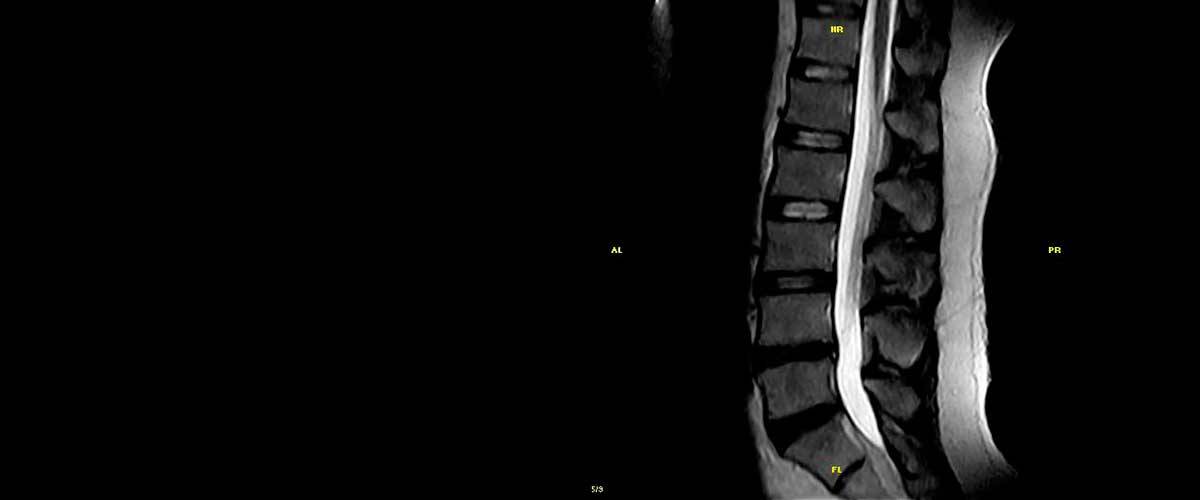

Contamos con equipos de resonancia magnética musculo-esquelética capaces de realizar exámenes con descarga de peso o bipedestación.

En nuestros centros se realizan estudios y diagnósticos de resonancia magnética musculo-esquelética

de Resonancia ,Magnética Musculo-Esquelética, de la marca italiana Esaote, es único en su diseño ya que nos permite realizar exámenes en bipedestación (el paciente estará de pie, para que se tenga otra perspectiva del comportamiento del cuerpo durante el examen).